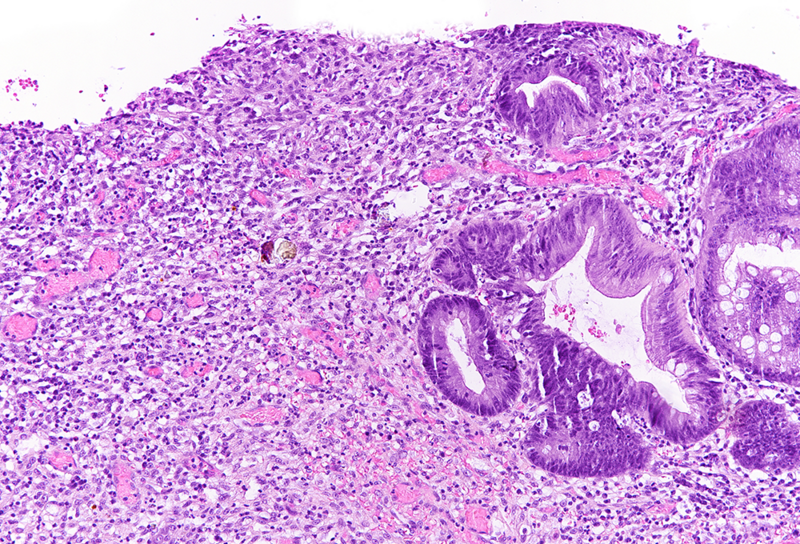

On macroscopy, multiple ulcers were visible on the mucosa of the colon. Histology showed ulcers with prominent granulation tissue, reaching the muscular wall of the bowel. They were surrounded by colonic mucosa with regenerative architectural changes (Panels A-B). In the ulcers and on the surface mucosa, yellow-pink polygonal foreign material with scale-like appearance was seen, which corresponded to the given sevelamer drug (Panels C-D).